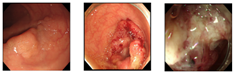

4. Experiments

Our dataset consisted of three types of images, which were used for training and testing our network. Sample images from our dataset can be seen in Figure 7, where Figure 7a shows colonoscopy images of a normal person, Figure 7b shows colonoscopy images containing an adenomatous polyp, and Figure 7c shows colonoscopy images containing a cancerous adenomatous polyp. As shown in Figure 7, the colon of a normal person is without any polyps in the mucosa. When a polyp develops in the colon of a normal person (see Figure 7b), it can develop into a relatively large adenomatous polyp (see Figure 7c). Adenocarcinoma of the adenomatous polyps develops into malignant tumors and become cancer. The shape and size of the polyps developed by the cancer appear in various forms without any specific rules (see Figure 7c).

Figure 7.

Endoscopy image type in this experiment. (a) Normal images; (b) adenoma images; (c) adenocarcinoma images.